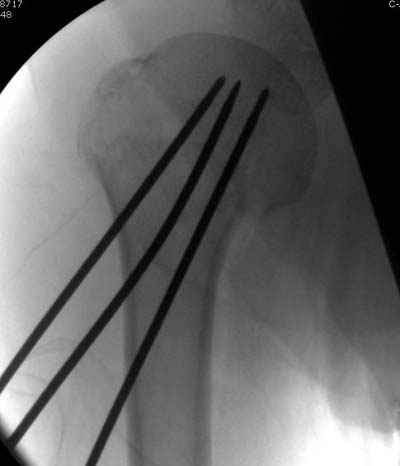

Спасибо за участие в дискуссии -перелом шейки плеча, для себя я прояснил многие технические моменты...

Посылаю послеоперационные Рг граммы.

Я и сам доволен результатом. В предпоследнем письме я кратко описал ход операции - закрыто репонировать не удалось( 2 недели с момента травмы и 1 неделя после неудачной репозиции) после удаления пучков спиц, пришлось сделать - 2см разрез на уровне перелома и с помощью периостального элеватора (золотое правило механики) *одеть* головку на дистальный отломок.

Спицы проводил через старые отверстия, вращая пучок импактором- направителем при его введении в головку.